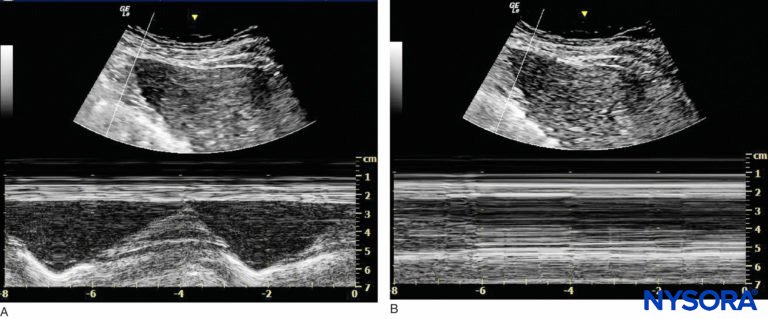

The function of the phrenic nerve can be assessed using ultrasound in M-mode during which a low-frequency curvilinear probe is positioned under the rib cage on the anterior axillary line to evaluate the hemidiaphragm motion (Figure 12). Of note, some authors have recommended using a combination of suprascapular nerve and axillary nerve block to provide postoperative analgesia with minimal motor block distal to the shoulder with a lower risk of phrenic nerve block and other complications of interscalene nerve block. The targeted nerves are small and may prove difficult to find in obese patient. Moreover, these nerve blocks will not provide surgical anesthesia. Another issue that must be considered is persistent phrenic nerve palsy. There is little agreement as to what causes persistent phrenic nerve palsy, but it seems to be at least in part related to inflammation and nerve entrapment rather than direct needle trauma. A contribution of cervical spine disease has been suggested. Other factors may be involved, as most patients in published series have been male, overweight or obese, and middle-aged.

FIGURE 12. Imaging of the right hemidiaphragm under the ribcage on the anterior line. (A) Before interscalene nerve block. (B) After interscalene nerve block with phrenic nerve block.